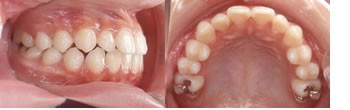

■治療前

乳臼歯が早く抜けて、奥歯が通常より手前に生えてしまいました。犬歯が生えるスペースが充分に取れていません。このままでは永久歯が生えそろうとでこぼこの歯の歯並びになってしまいますので、犬歯が生える前に奥歯を後ろに下げる治療を行いました。

■治療後

犬歯がきちんと生えて、きれいな永久歯の歯並びができあがりました。